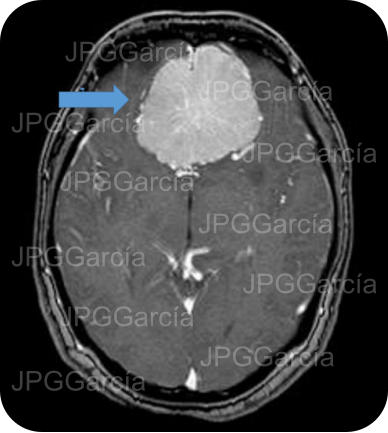

Tumor del plano esfenoidal clasificado por imagen como Meningioma visto a través de resonancia magnética cortes axial y coronal